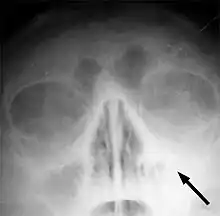

Frontal sinusitis -

X-ray of left-sided maxillary sinusitis marked by an arrow. There is lack of the air transparency indicating fluid in contrast to the other side.